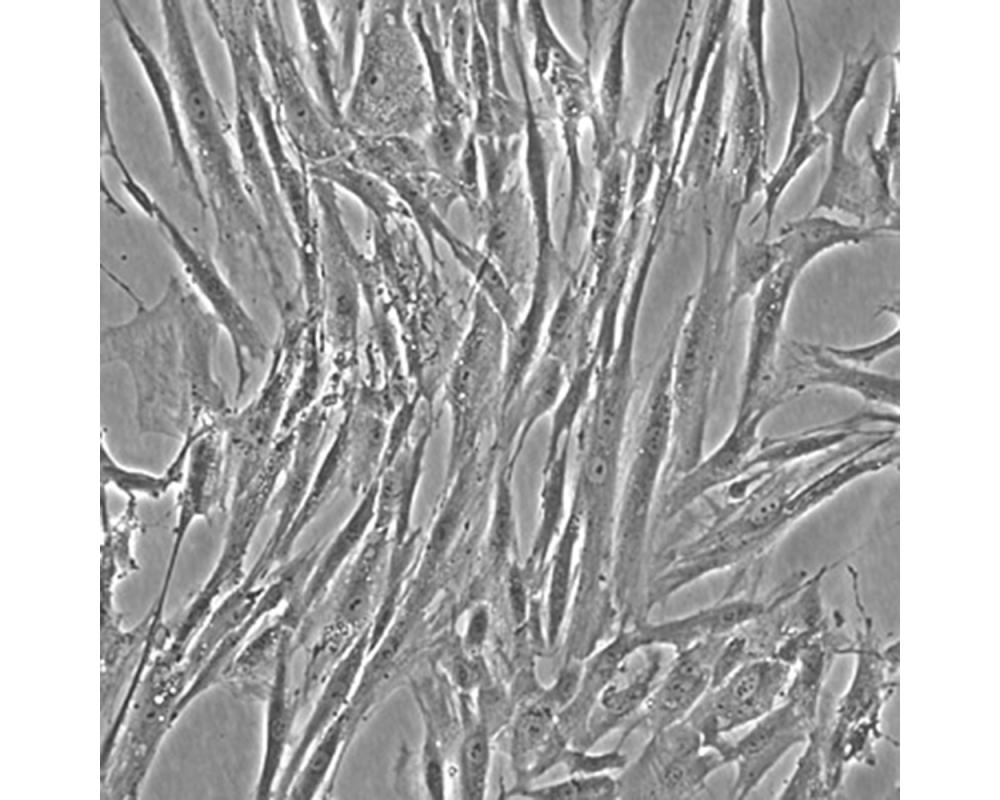

產(chǎn)品名稱 Hs 606.T

中文名稱 人乳腺癌細(xì)胞

組織來源 乳腺癌;女性

生長特性 貼壁